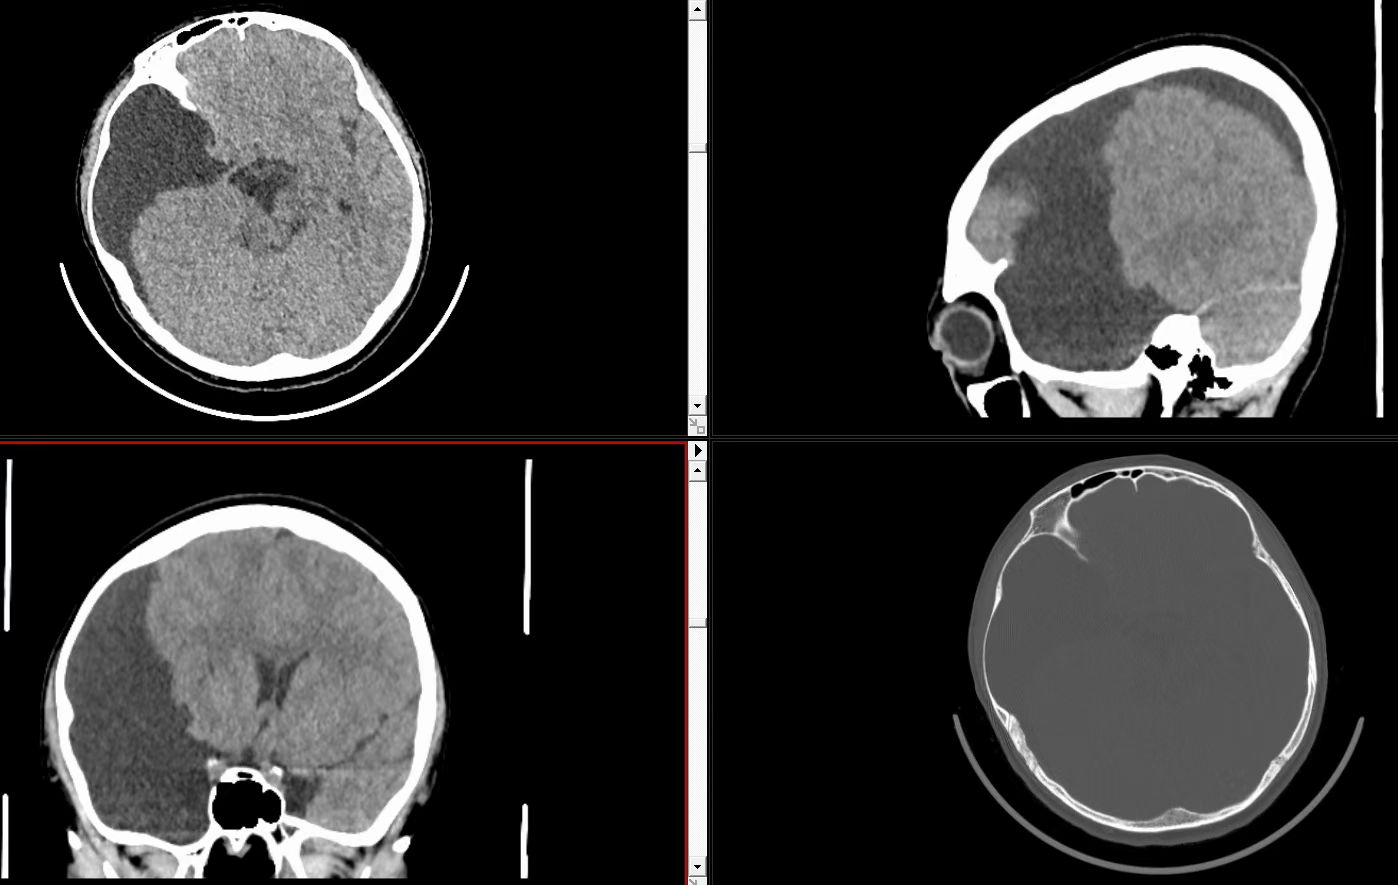

住院后完善颅脑CT,对比以前囊肿体积和范围都有增大,并且中线受压偏移,颅骨侵蚀变薄。

2025.7月颅脑CT(囊肿体积增大,侵蚀颅骨,中线移位)